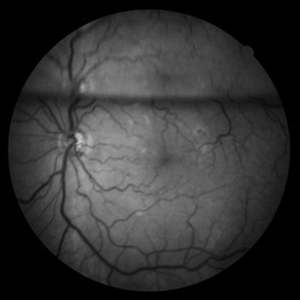

BRVO

Color fundus and red free photographs OD. Ghost vessels and shunts are shown.

Photographer: Lourdes Guambo MD

Condition/keywords: branch retinal vein occlusion (BRVO), ghost vessels, occlusion of retinal vein, shunts vessels